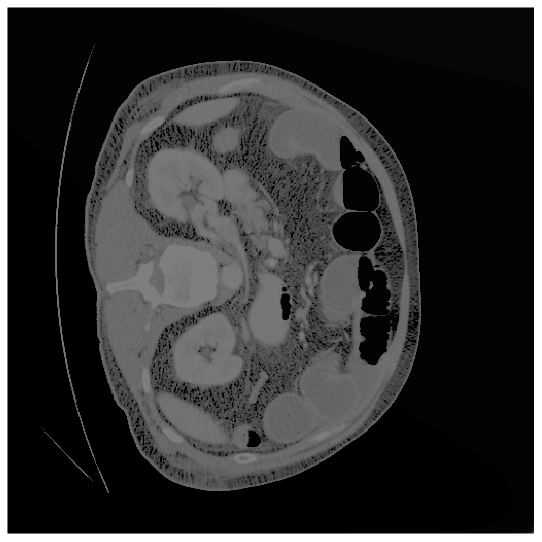

Our model is evaluated on the Synapse [25] and ACDC [24] datasets. Synapse is an abdominal CT image dataset with 30 images containing eight organs: the aorta, gallbladder (GB), left kidney (KL), right kidney (KR), liver, pancreas (PC), spleen (SP), and stomach (SM). 18 and 12 scans are used for training and evaluation, respectively. ACDC provides MRI data containing three organs of 100 patients: the right ventricle (RV), left ventricle (LV), and myocardium (Myo). 70 images for training, 10 for validation, and 20 images for evaluation are used.

where and denote the fuzzy window patch extracted from the original image and the pixel at coordinates in the original image , respectively. is the scaling factor defined as the ratio of the desired uniform variance to the fuzzy variance , and is the translation factor, where represents the fuzzy mean. In the logarithmic model, the operator represents scalar multiplication. The membership function calculator, , is weighted based on how each transformed fuzzy window contributes to the final enhanced image. As a result, the enhanced image exhibits improved quality and a distinct feature distribution compared to the original image. The original and enhanced images are shown in Fig. 14(a) and Fig. 14(b), respectively. As shown in Fig. 14(b), the image quality is enhanced by Eq. (12), emphasizing the organ’s attributes, including shape and intensity. Consequently, previously subtle features in Fig. 14(a), become more pronounced in Fig. 14(b). When these two images are processed through their respective encoders, they generate feature maps characterized by diverse feature distributions and unique information. In other words, the boundary information is better preserved in the original image, while the enhanced image highlights the object’s details. Thus, cross-learning the information from both images leads to improved performance. Please kindly refer to [36] for more details.